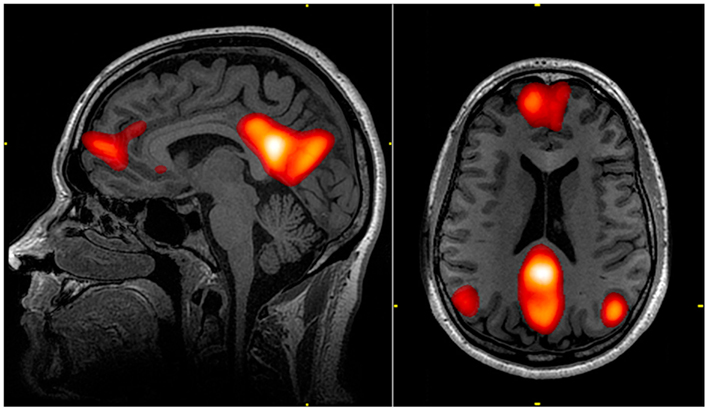

Это не метафора. Исследование 2009 года с позитронно-эмиссионной томографией (почти 100 участников) показало, что в ключевых зонах системы вознаграждения мозга у людей с СДВГ значимо снижена активность дофаминовых рецепторов [1]. Те же авторы потом показали, что этот дефицит напрямую связан с проблемами мотивации, причём только у группы с СДВГ, у контрольной группы такой связи не было [2].

Ещё в 2001 году группа нейроучёных провела ПЭТ-исследование и обнаружила, что интенсивное удовольствие от музыки, те самые «мурашки», сопровождается всплеском активности в зонах вознаграждения мозга. Тех же самых, которые реагируют на еду, секс и другие базовые награды. Эта работа набрала больше 4000 цитирований и стала отправной точкой для целого направления [7]. Десять лет спустя, в 2011 году, с помощью более точного ПЭТ-сканирования впервые показали, что при прослушивании музыки в мозге реально выделяется дофамин [8]. Музыка это единственный абстрактный стимул, который запускает ту же нейрохимическую реакцию, что и базовые потребности.

А в 2019 году поставили окончательную точку: в двойном слепом эксперименте дали одним участникам предшественник дофамина, удовольствие от музыки усилилось. Дали другим антагонист, снизилось. Каузальное доказательство: дофамин напрямую управляет тем, как мы переживаем музыку [9].